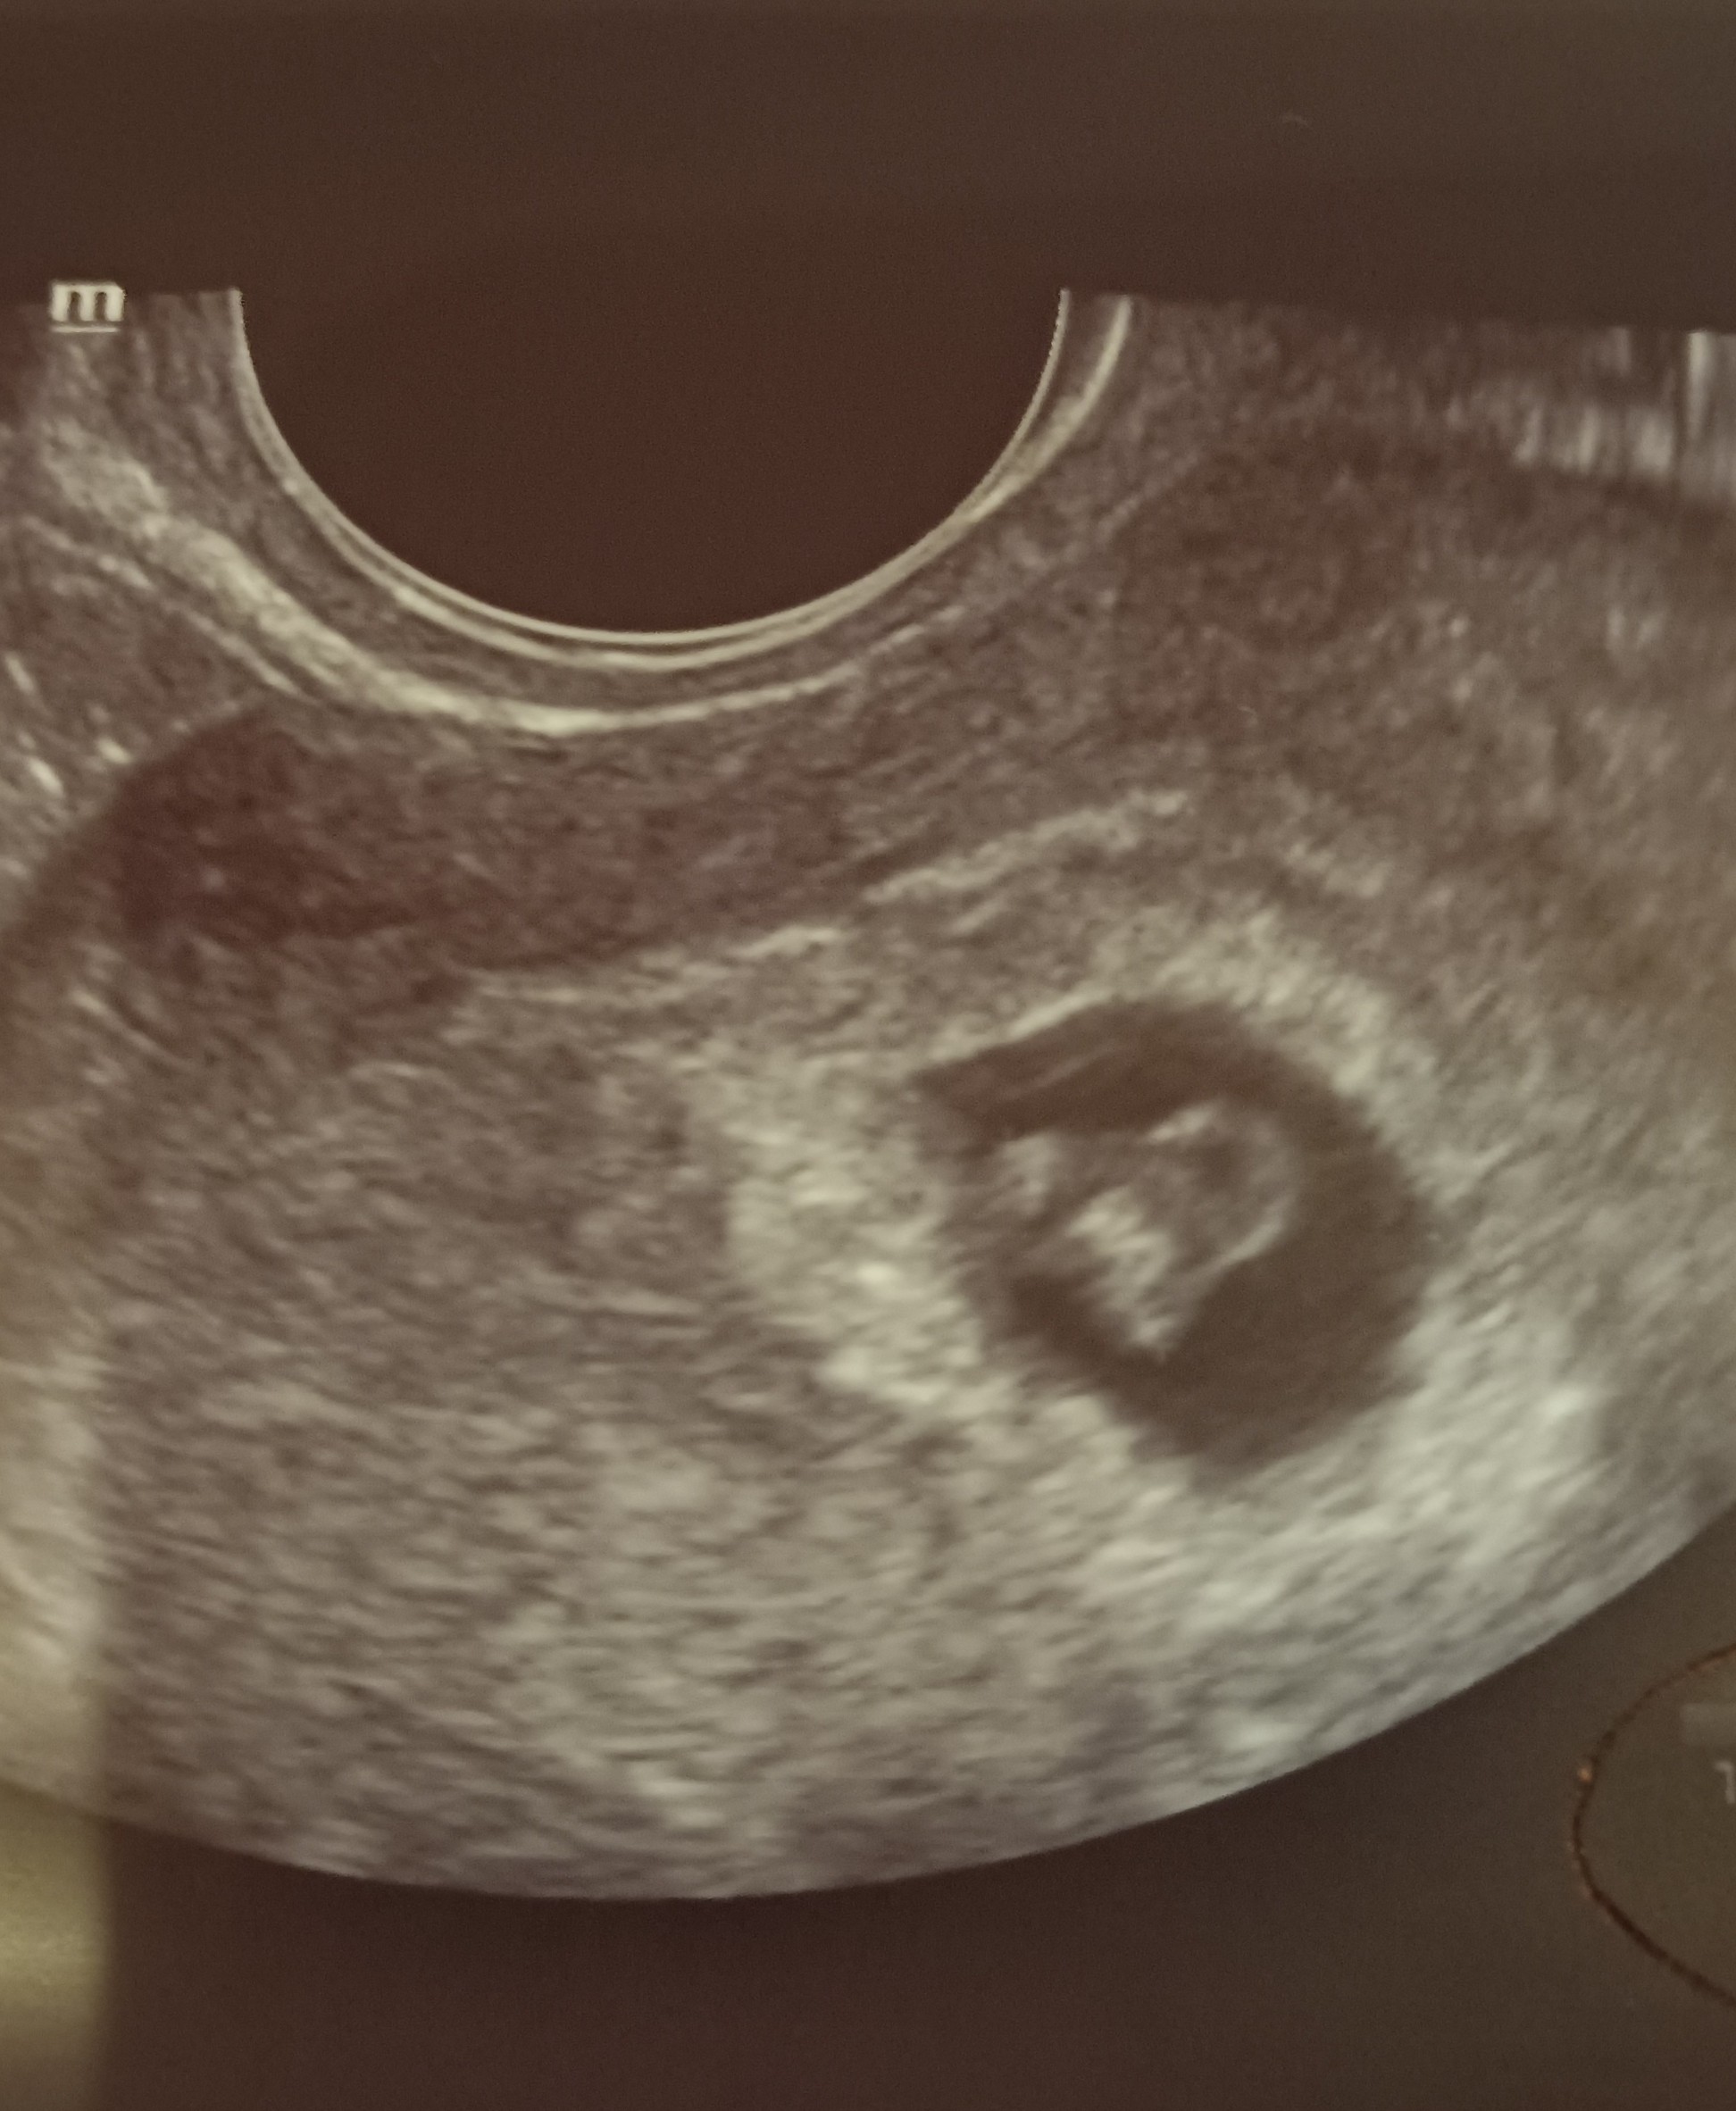

Ja już po wizycie🥰 serduszko pięknie bije🥰 mąż mógł wejść i też zobaczyć malucha na USG. Tak się cieszę!🙂

Załączniki

• IMG_20211206_194209.jpg

IMG_20211206_194209.jpg

563,1 KB · Wyświetleń: 112